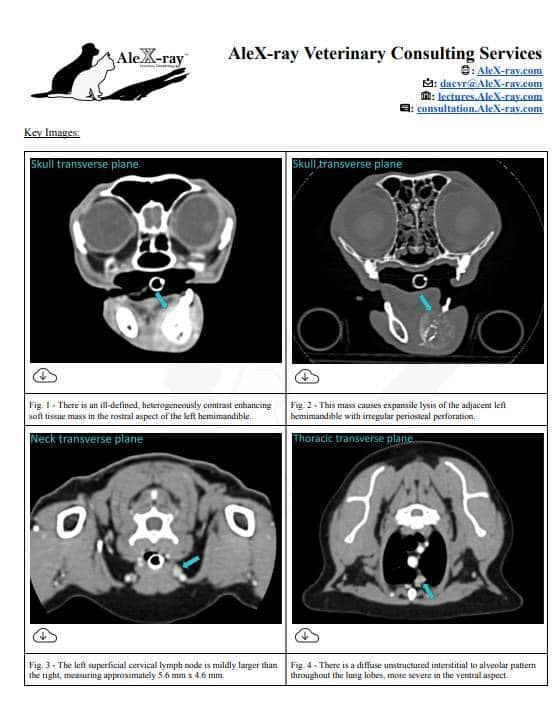

口腔鱗狀上皮細胞癌(SCC)的貓咪,術前的電腦斷層(CT)掃描主人希望能趕在特定時間內完成判讀。